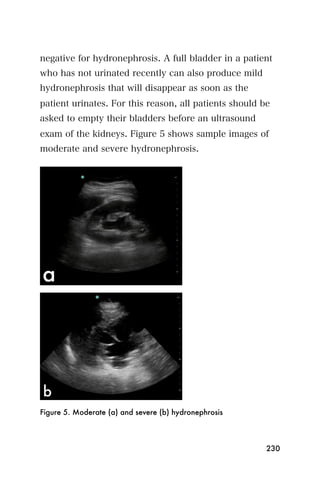

Measuring gestational age

When viewing a baby ultrasound, the sonographer can

measure how old it is using ultrasound. This is much